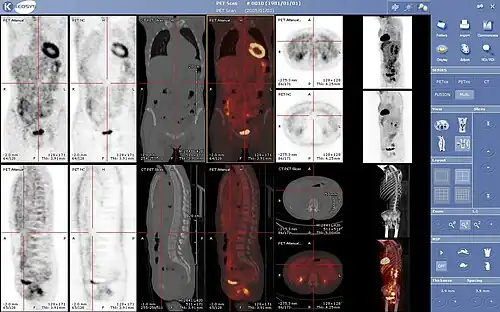

PET scanners can incorporate a computed tomography scanner (CT) and are known as PET–CT scanners. PET scan images can be reconstructed using a CT scan performed using one scanner during the same session.

Combination of PET with CT or MRI

PET scans are increasingly read alongside CT or MRI scans, with the combination (co-registration) giving both anatomic and metabolic information (i.e., what the structure is, and what it is doing biochemically). Because PET imaging is most useful in combination with anatomical imaging, such as CT, modern PET scanners are now available with integrated high-end multi-detector-row CT scanners (PET–CT). Because the two scans can be performed in immediate sequence during the same session, with the patient not changing position between the two types of scans, the two sets of images are more precisely registered, so that areas of abnormality on the PET imaging can be more perfectly correlated with anatomy on the CT images. This is very useful in showing detailed views of moving organs or structures with higher anatomical variation, which is more common outside the brain.